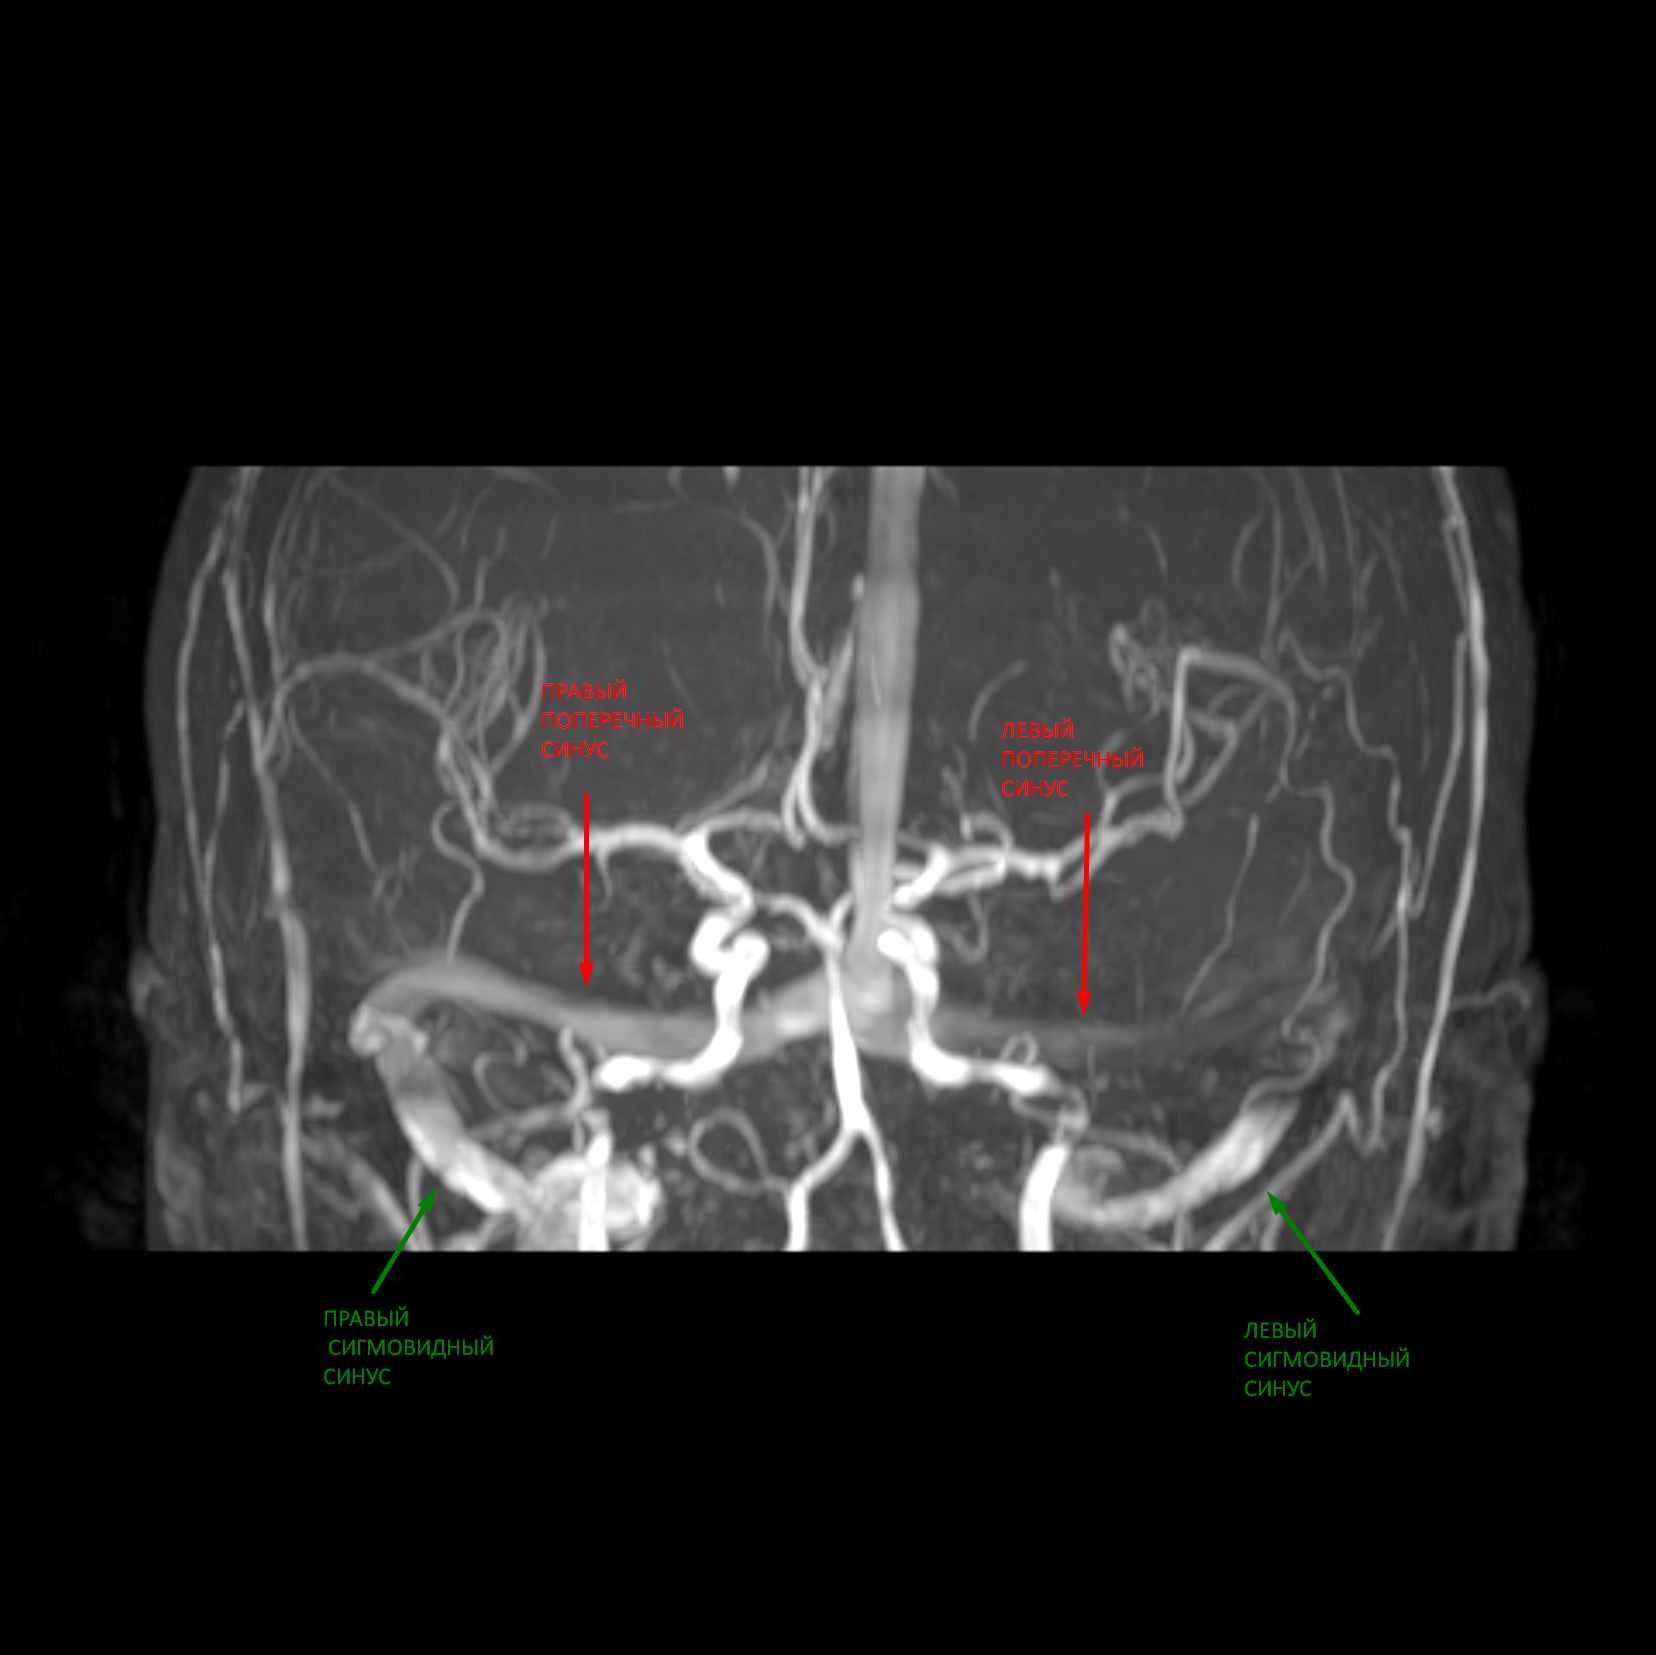

На МР-ангиограммах: cигнал от кровотока по позвоночным артериям симметричный: около 3,5 мм. Ход позвоночных артерий типичный. Сигнал от кровотока по внутренним сонным артериям (ВСА) симметричный: около 4,5 мм. Ход ВСА не изменен. Базилярная артерия имеет типичный ход, просвет равномерный. Виллизиев круг симметричен: выявлена передняя соединительная артерия, кровоток по задним соединительным артериям не визуализируется - вариант развития. Венозный отток сохранен, сигнал от кровотока по поперечным и сигмовидным синусам минимально асимметричный (c доминированием справа).

3.Легкая асимметрия венозного оттока по базальным синусам и внутренним яремным венам (в пределах индивидуальных особенностей развития).

Пояснение: изменения сигнальных характеристик венозного оттока не выявлено. Визуализируется асимметрия, что соответствует индивидуальным особенностям развития (см. рис.3).